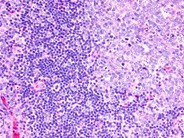

Toxoplasmosis is a common parasitic infection which is usually asymptomatic. Symptoms, when present, are typically those of a flu-like illness with fever, muscle aches, and swollen, tender lymph nodes. Histologically, the involved nodes show follicular hyperplasia and diffuse proliferation of epitheliod histiocytes. The image shown illustrates the follicular hyperplasia and expansion of the interfollicular area by pale appearing cells.